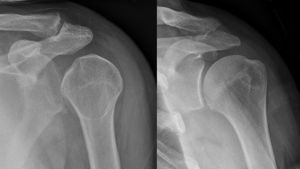

Posterior shoulder dislocation

- Plain film X-ray

- Scapular "Y" view shows humeral head in posterior position

- Lack of normal overlap of humeral head and glenoid fossa

- "Light bulb sign" - fixed internal rotation makes for light bulb appearance of humeral head on AP